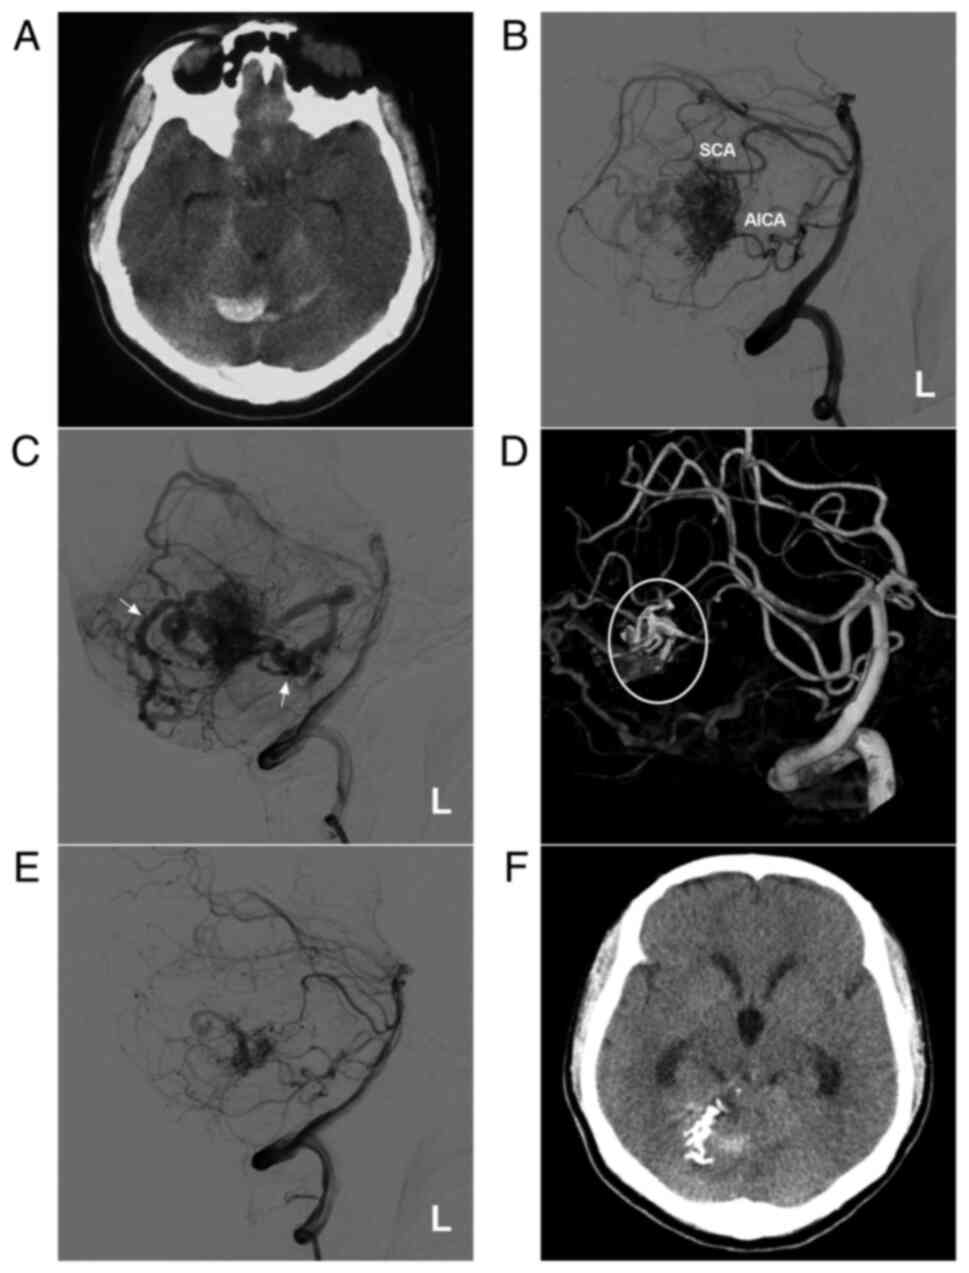

Figure 3

AVM in the middle cerebellum with a mixed blood supply from the SCA and AICA. (A) CT scan showing a subarachnoid hemorrhage and right cerebellar vermis hematoma. (B) DSA of the left vertebral artery shows the AVM supplied by the SCA and AICA. (C) DSA of the late arterial stage shows the draining veins (arrows). (D) Three-dimensional reconstruction DSA showing Onyx™ casting (ellipse) through the SCA. (E) DSA after embolization showing a small amount of residual AVM nidus. (F) Post-operative CT scan showing that the hemorrhage was absorbed, but had a dilated ventricle. The case presented in this figure was a 20-year-old female who had a sudden headache. EVT was performed. No EVT complication was observed. Currently, the woman exhibits normal healthy features and attends university. Radiotherapy was suggested. AICA, anterior superior cerebellar artery; AVM, arteriovenous malformation; CT, computed tomography; DSA, digital subtraction angiography; L, left; SCA, superior cerebellar artery.